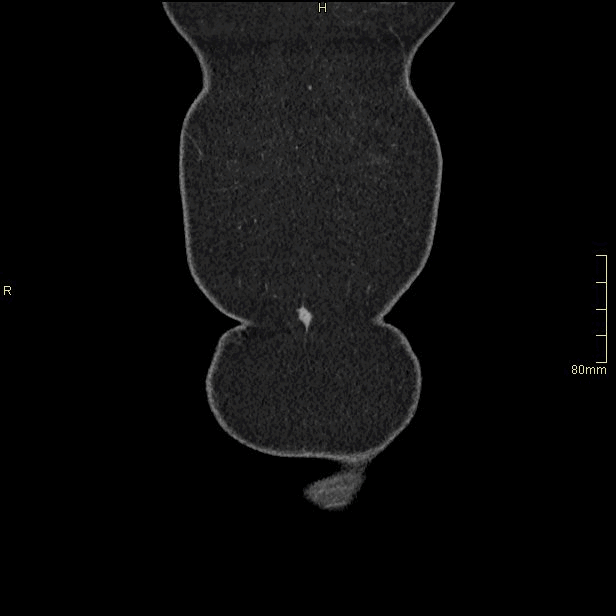

For patients over the age of 40, a non contrast KUB, and seperate nephrogenic and excretory (delayed) phases will be performed. For all patients under the age of 40, a non contrast KUB and a COMBINED dual nephrogenic/excretory phase will be performed. Image examples of this can be seen below.

Under 40 Years of Age

CT Urogram- Nephrogenic + Excretory Phase (Coronal)